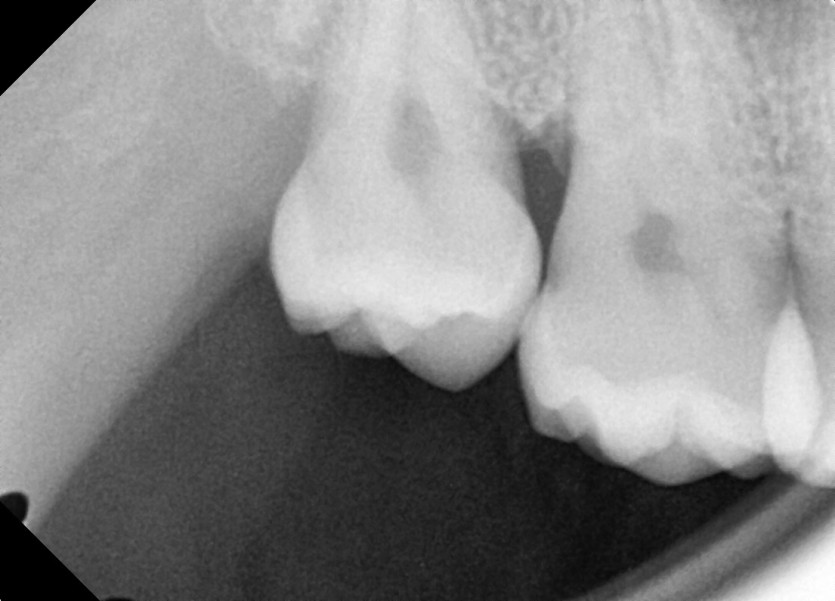

#18,48 사랑니 발치

구강 외과 전문의가 당일 발치했습니다.